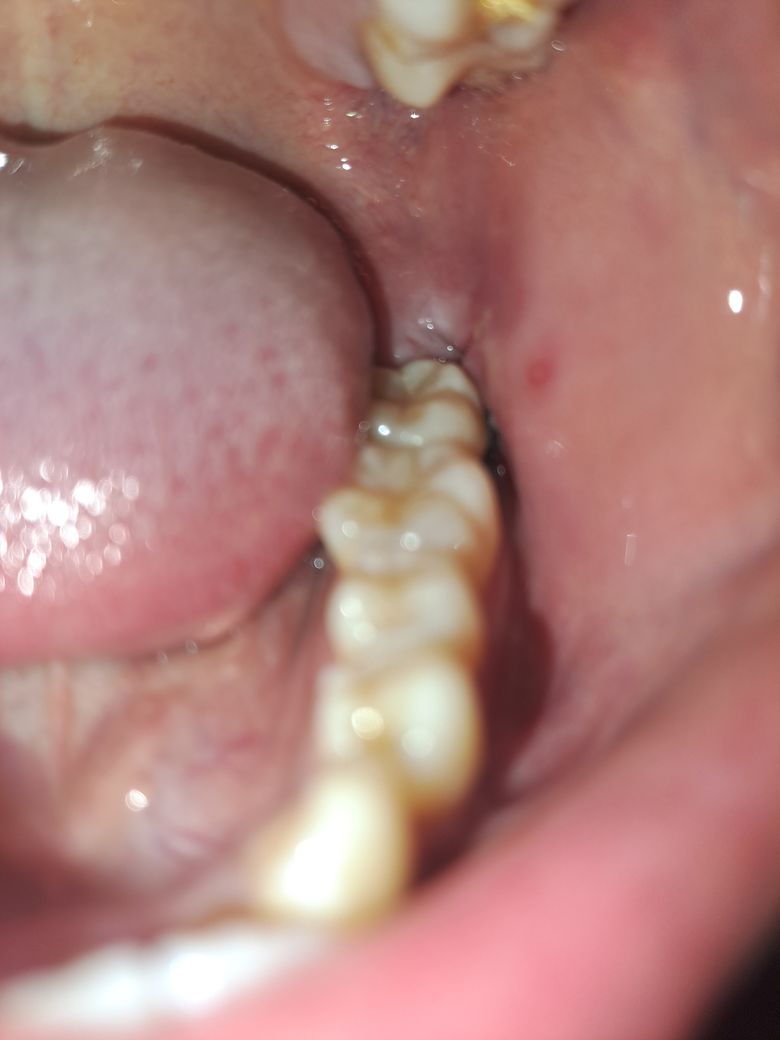

사랑니 발치후 음식을 씹으면 고통스러운데 왜일까요..?

발치 4일차이고 3일차일때 드라이소켓인지 묻는 글 올렸었습니다. 의사분들 답변보고 헥사메딘 가글도 사서 잘 쓰고 있는데요...

어제 저녁즈음부터 음식을 씹으면 발치부와 어금니쪽이 매우 고통스럽습니다...

당연히 발치부 반대쪽으로만 씹는데도 욱씬거리고 말로 표현할 수 없는 통증이 밀려오네요....

현재 어금니가 아주 미세하게 조금씩 흔들리고 있고, 입을 다물면서 어금니가 눌리면 좀 아프고, 벌릴때 밀리는게 느껴진다 해야할까요...

• 1번 째 사진